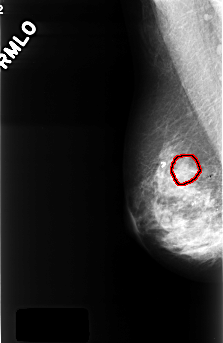

C_0394_1.RIGHT_CC

FILE: C_0394_1.RIGHT_CC.OVERLAY

TOTAL_ABNORMALITIES 1

ABNORMALITY 1

LESION_TYPE CALCIFICATION TYPE AMORPHOUS DISTRIBUTION CLUSTERED

ASSESSMENT 4

SUBTLETY 2

PATHOLOGY BENIGN

TOTAL_OUTLINES 1

BOUNDARY